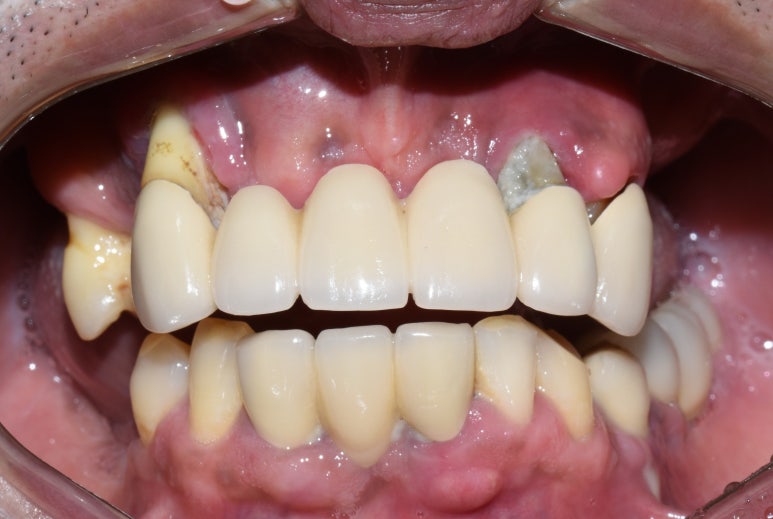

- 오래된 상악틀니 → 2. 틀니제거시 모습 → 3.상악전체 임플란트

- 오래된 틀니를 새 전체틀니로, 아래앞니 부위는 임플란트

오래된 상악틀니를 상악 전체 틀니로 교체

아래 앞니부위 임플란트까지 한 후

- 위의 틀니와 아래 어금니 임플란트를 5년쓰시다가

어금니 임플란트가 너무 편하고 뺐다 꼈다하는 틀니가 귀찮다고 하셔서 위 전체 임플란트

-

원래 치아상태 ->2. 위 틀니, 하악어금니 임플란트 ->3. 상악도 전체 임플란트로.